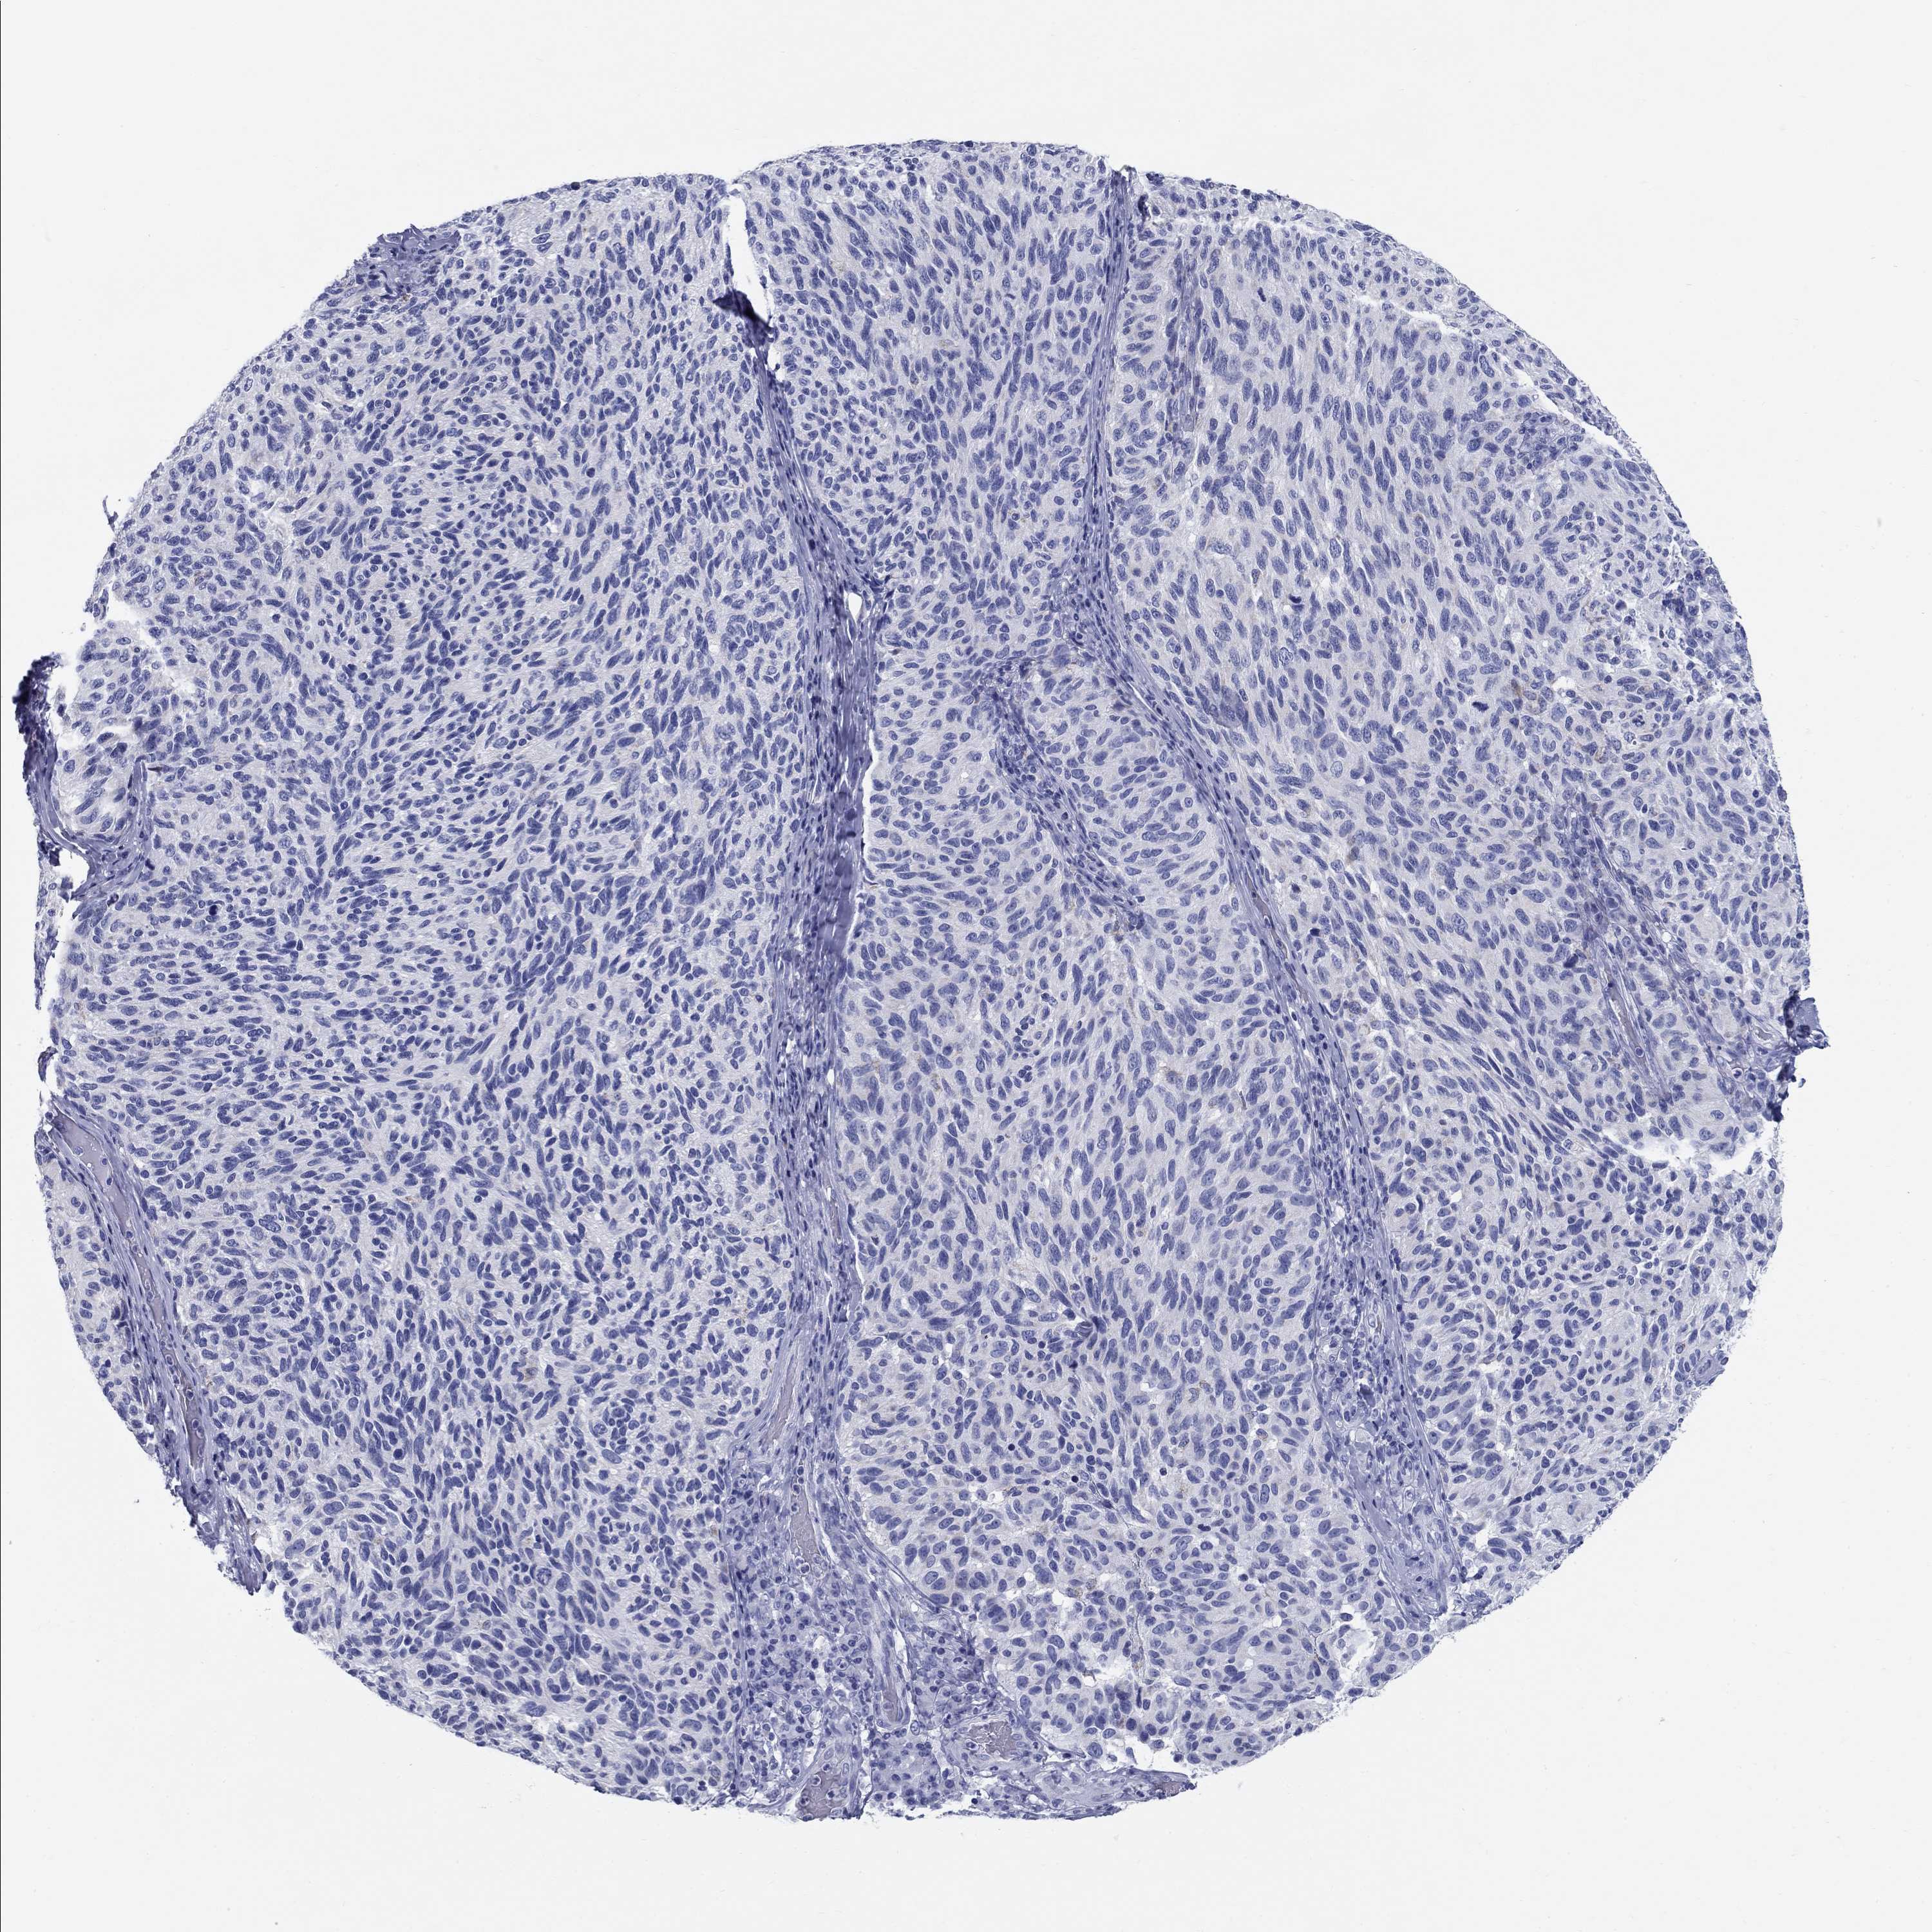

MELANOMA - Protein expressioni

A mouse-over function shows sample information and annotation data. Click on an image to view it in a full screen mode. Samples can be filtered based on level of antibody staining by selecting one or several of the following categories: high, medium, low and not detected. The assay and annotation is described here.

Note that samples used for immunohistochemistry by the Human Protein Atlas do not correspond to samples in the TCGA dataset.

Antibody stainingi

Antibody staining in the annotated cell types in the current human tissue is reported as not detected, low, medium, or high, based on conventional immunohistochemistry profiling in selected tissues. This score is based on the combination of the staining intensity and fraction of stained cells.

Each image is clickable and will lead to virtual microscopy that enables deeper exploration of all samples and also displays staining intensity scores, fraction scores and subcellular localization as well as patient and tissue information for each sample.

Antibody HPA000728

Antibody HPA076321

Malignant melanoma, NOS

Malignant melanoma, Metastatic site